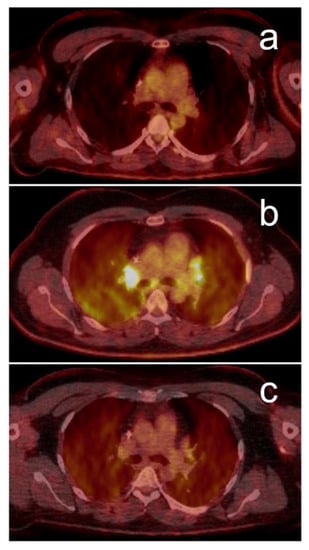

- Humbert, O.; Cadour, N.; Paquet, M.; Schiappa, R.; Poudenx, M.; Chardin, D.; Borchiellini, D.; Benisvy, D.; Ouvrier, M.J.; Zwarthoed, C.; et al. 18FDG PET/CT in the early assessment of non-small cell lung cancer response to immunotherapy: Frequency and clinical significance of atypical evolutive patterns. Eur. J. Nucl. Med. Mol. Imaging 2020, 47, 1158–1167. [Google Scholar] [CrossRef]

- Goldfarb, L.; Duchemann, B.; Chouahnia, K.; Zelek, L.; Soussan, M. Monitoring anti-PD-1-based immunotherapy in non-small cell lung cancer with FDG PET: Introduction of iPERCIST. EJNMMI Res. 2019, 9, 8. [Google Scholar] [CrossRef]

- Castello, A.; Rossi, S.; Mazziotti, E.; Toschi, L.; Lopci, E. Hyperprogressive Disease in Patients with Non–Small Cell Lung Cancer Treated with Checkpoint Inhibitors: The Role of 18 F-FDG PET/CT. J. Nucl. Med. 2020, 61, 821–826. [Google Scholar] [CrossRef] [PubMed]